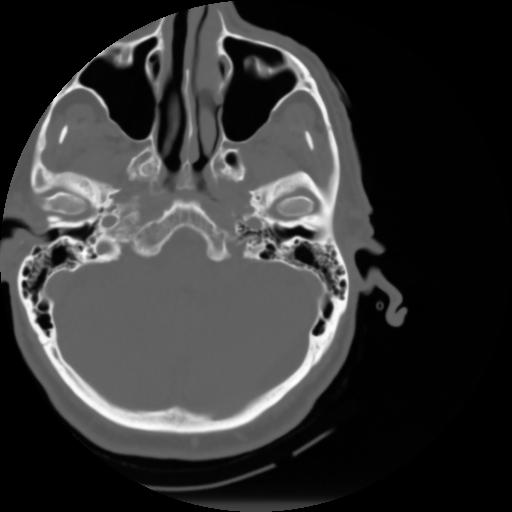

3 CEREBRO,,Axial,3.0,CEREBRO,,